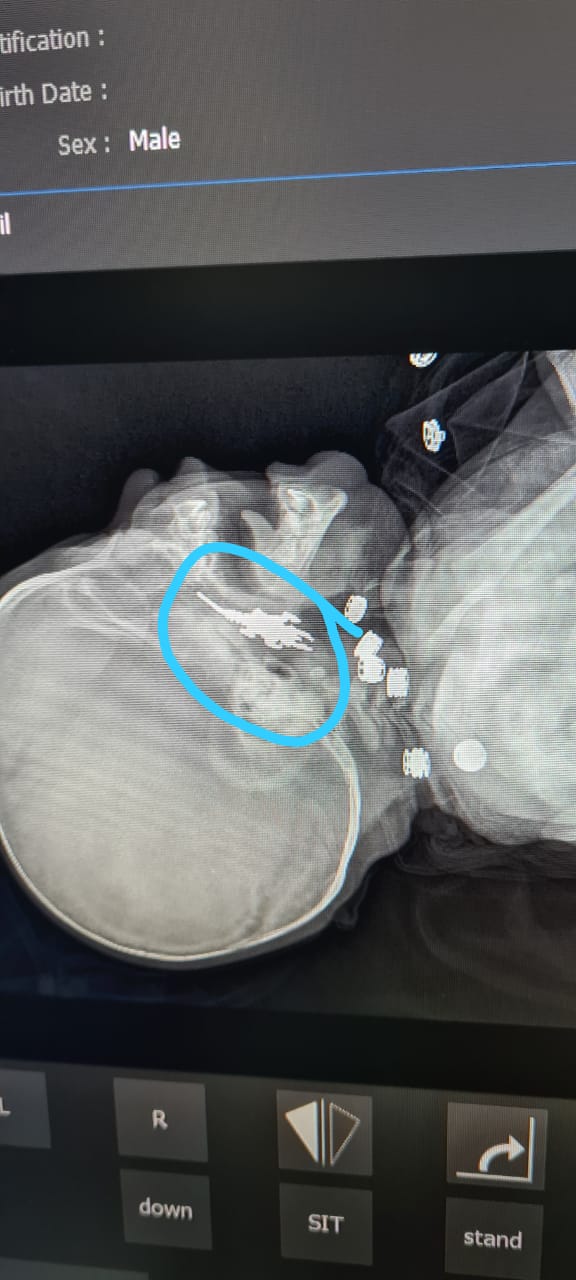

Врачи Мангистау достали брелок из носоглотки младенца

Брелок в виде динозавра застрял в носоглотке трехмесячного ребенка. Врачи смогли вовремя его вытащить. Об этом сообщили в Мангистауской областной многопрофильной детской больнице.

Фото предоставлено Мангистауской областной многопрофильной детской больницей

Младенца в экстренном порядке доставили из Жанаозена вчера, 20 января. В носоглотке трехмесячного ребенка застрял инородный предмет. Попытки врачей Жанаозенской городской больницы достать его оказались безуспешны.

В Мангистауской областной многопрофильной детской больнице врачи оценили серьезность ситуации. Врач Казбек Шукуров принял решение сделать ребенку анестезию и эндоскопическим путем успешно вытащил предмет из носоглотки младенца. Инородным телом оказался брелок в виде динозавра.